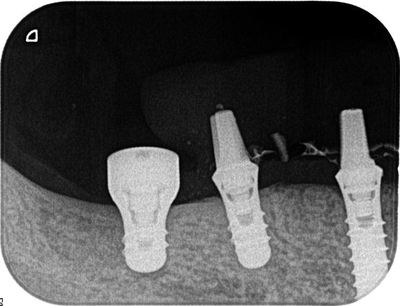

埋入後のデンタルレントゲンです。